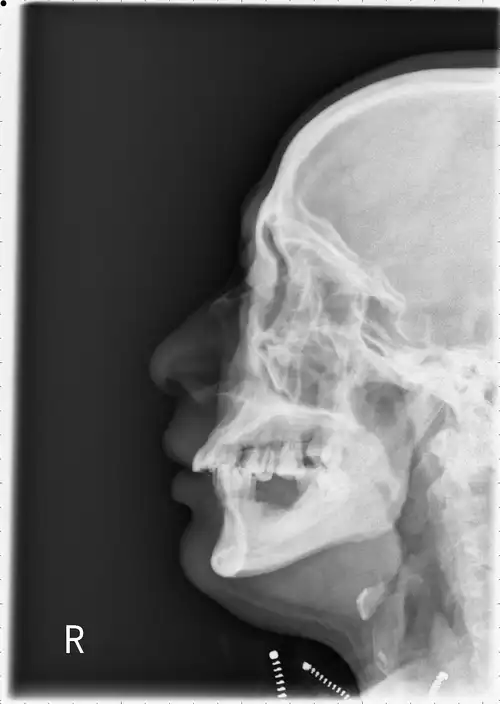

根据鼻面部外伤史,鼻部的视诊,触诊和鼻腔的检查,结合鼻骨x线侧位摄片

和大家分享一个鼻骨发育异常的